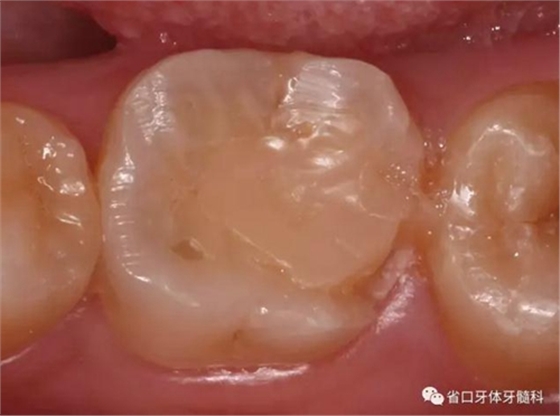

圖5 根管治療術后17個月復查口內照:46遠中邊緣嵴少許折裂

圖6 嵌體預備后